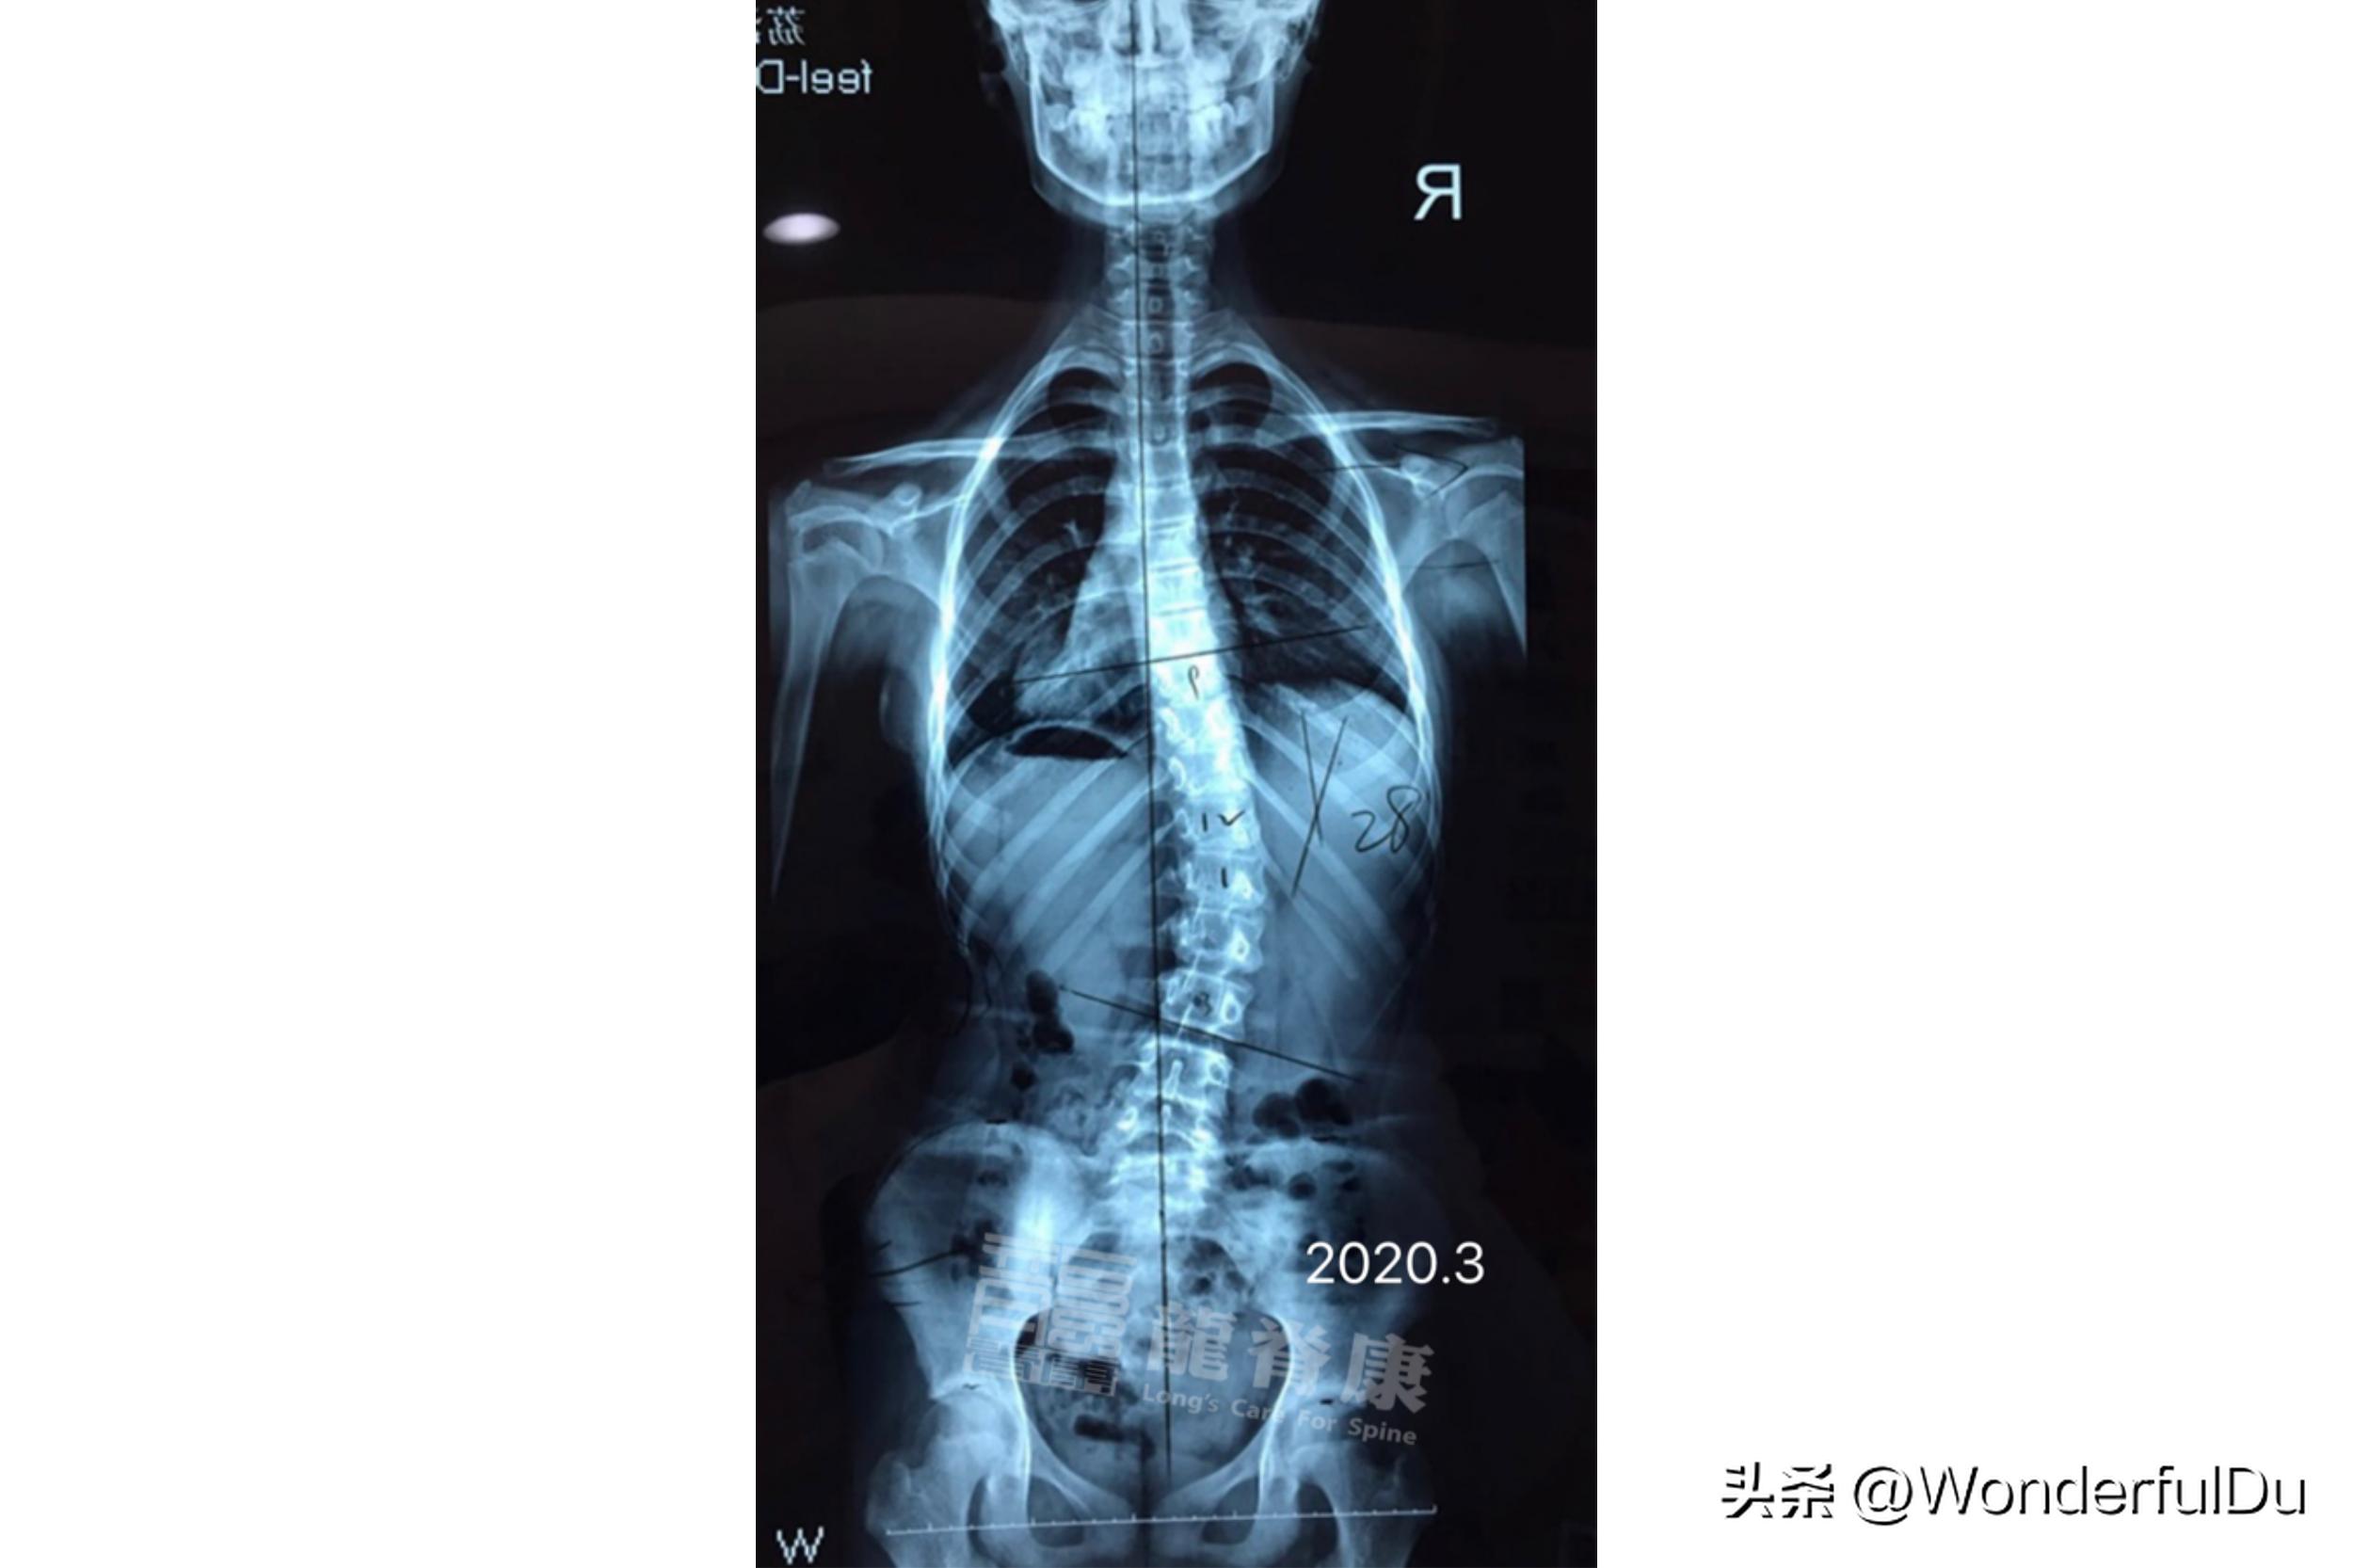

2019年的时候,家长发现小蓝体态异常,外院拍片确诊脊柱侧弯,当下定制国产支具及每周训练3次,持续半年后,复查拍片发现侧弯度数 反而增大 ,外院建议转诊,在2020年3月来龙脊康门诊进一步治疗。

经体查发现,小蓝右侧胸腰交界隆起,剃刀背9°, 骨盆左高右低 , 长短脚 ,明显扁平足,外院x光提示以T12为中心向右侧凸,Cobb角为28°。

于是我们建议孩子进行7D疗法,定制鞋垫,进行施罗斯及运康锻炼。半年后拍片复查 侧弯角度从28°减为10° ,右侧胸腰交界 剃刀背从9°减为5° 。一直到现在连续3年复查,其侧弯度数及剃刀背 基本稳定 。